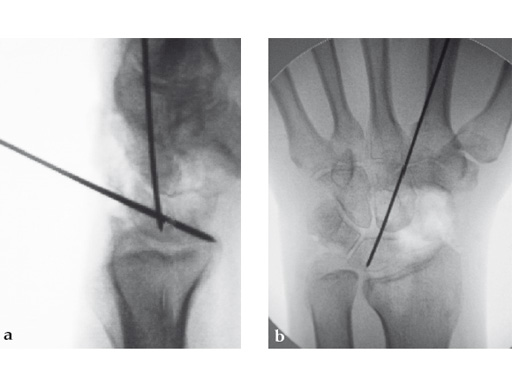

Case 1: SNAC wrist stage 3. Operative procedure and technical details.

Case provided by Ladislav Nagy, Zrich, Switzerland, and Fiesky Nez, Valencia, Venezuela.

Fig 2ab Dorsal intercalated segment instability correction and K-wire fixation.

Fig 3ab Bone debridement. Guide positioning and fixation.

Fig 3c Bone debridement. Guide positioning and fixation.

Fig 4c Once the carpal junctions have been putting closer by the new reduction-compression guide, reaming is done.